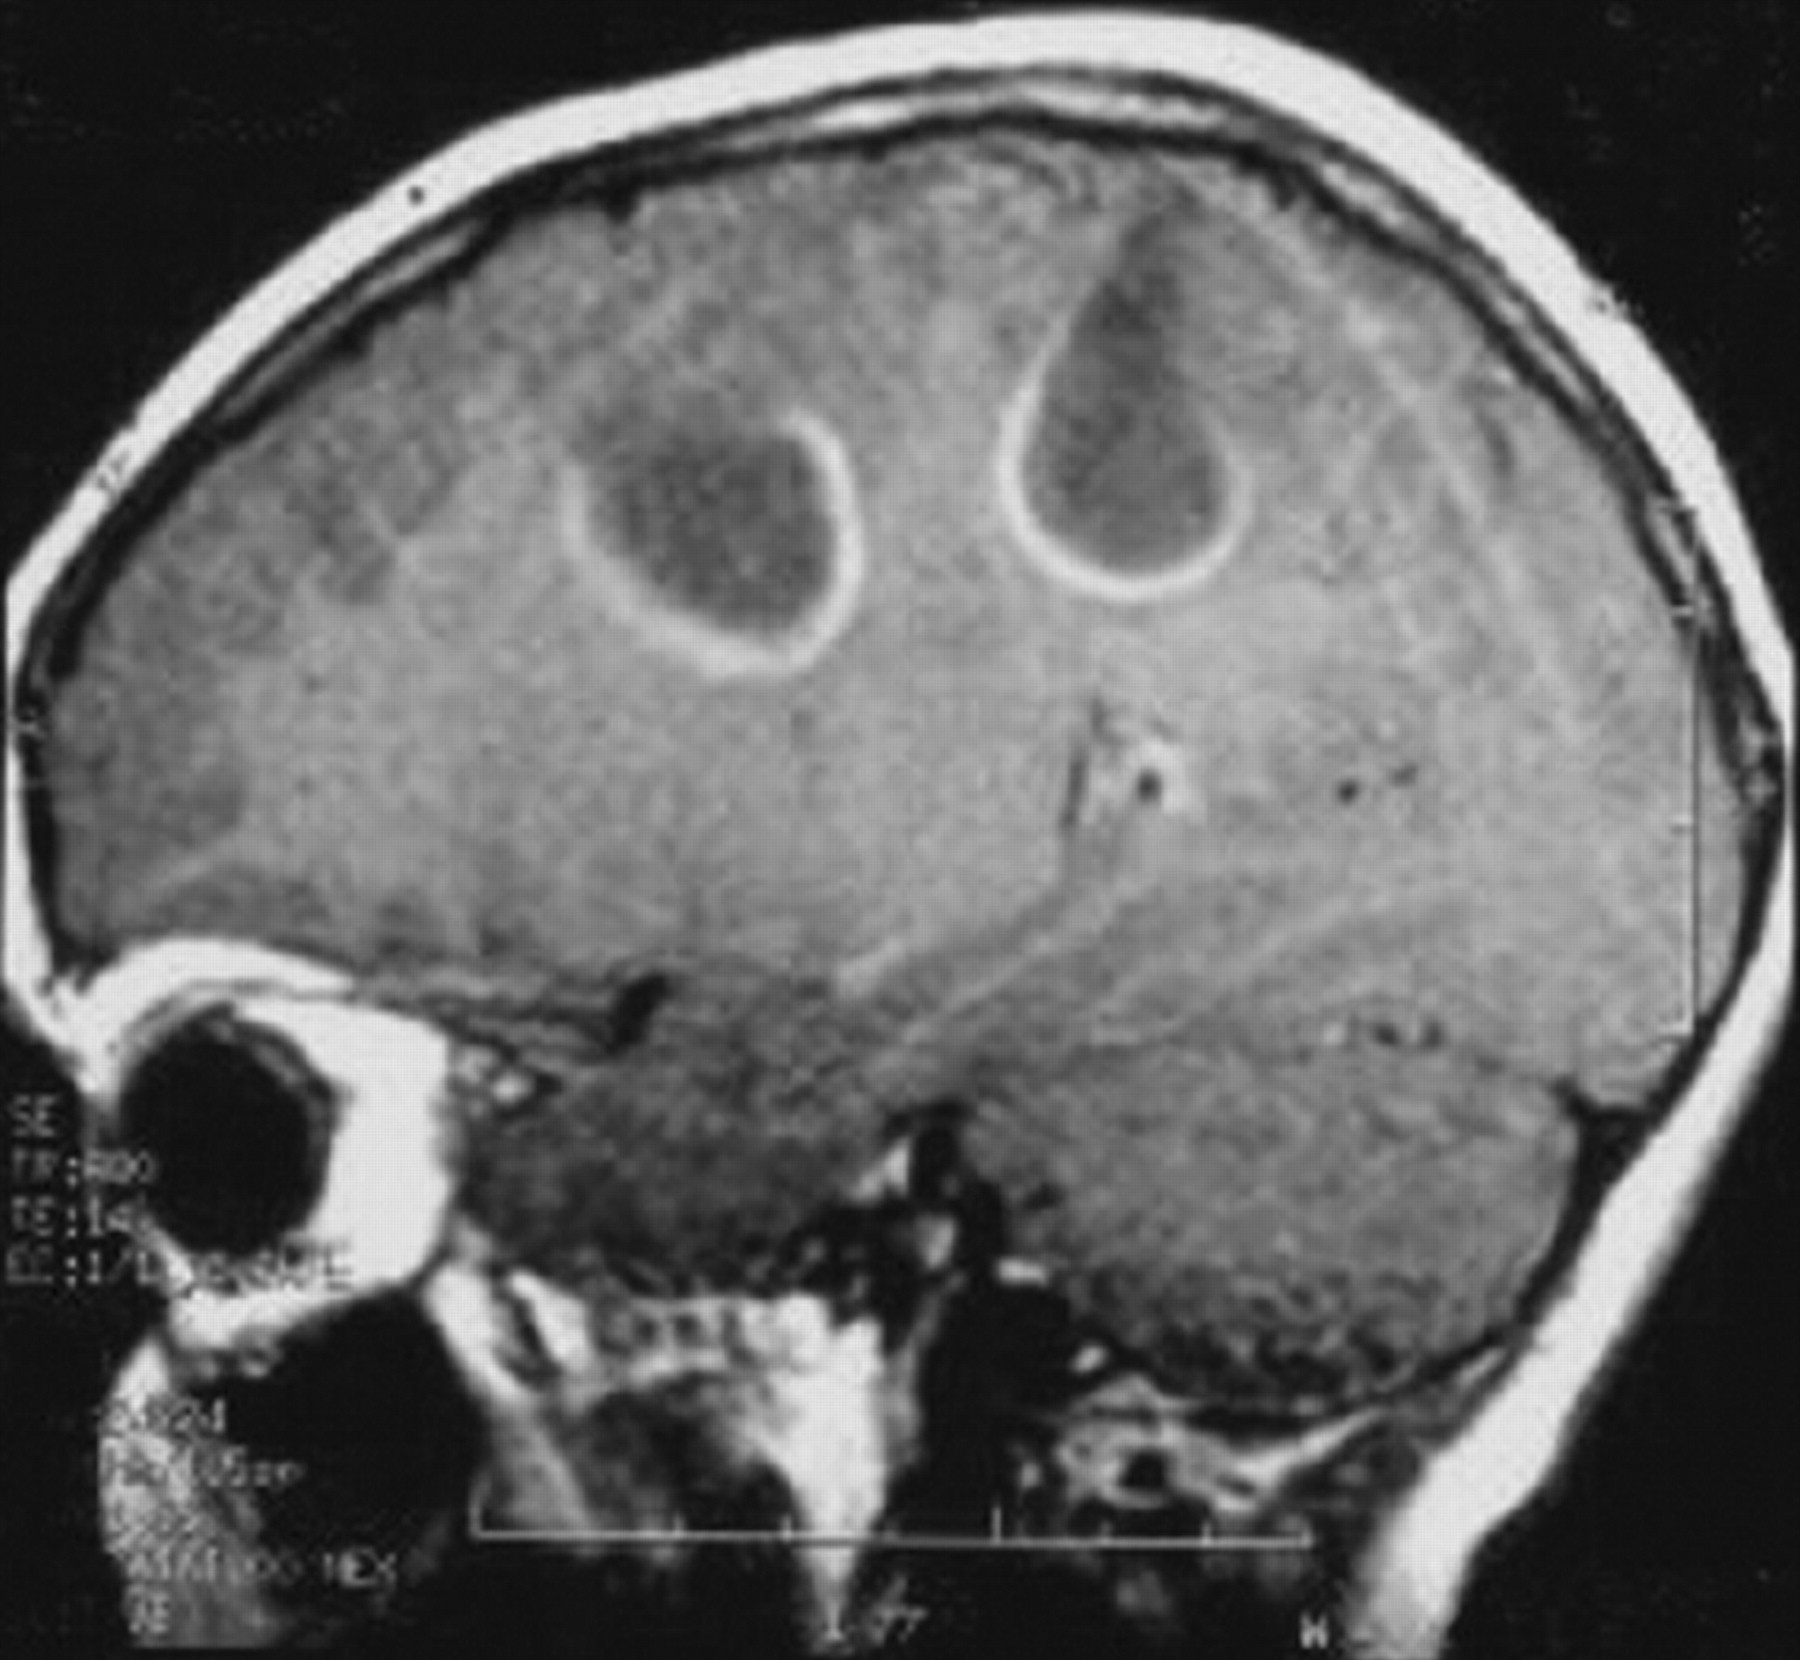

提出了四种模式的大脑参与描述ADEM的磁共振成像结果21:1)ADEM小病变(少于5毫米;图1);2)ADEM大支流,块状病变,簇状或频繁广泛perilesional水肿和质量效应(图2);3)ADEM附加对称bithalamic参与(图3);和4)急性出血性脑脊髓炎(咳咳),当一些出血的证据可以确定大脱髓鞘病变(图4)。核磁共振成像模式似乎并不与任何特定的结果或残疾,作为大型儿童群体中观察到,21因为大多数病变往往解决后续成像研究。21日,32然而,这种分类可能是有用的在考虑的鉴别诊断ADEM和可能有助于识别那些孩子来说,初始ADEM-phenotype真的是第一个女士的表现。

钆增强病变的发生率在t1序列非常变量外,可能取决于炎症阶段。31日,33岁的34钆增强病变在30 - 100%的患者被描述。21日,35岁的36增强的模式是可变的;完整或不完整的环形(图5),结节性、旋转的或参差不齐的模式被描述。36-38脑膜增强大脑或脊髓的不寻常。